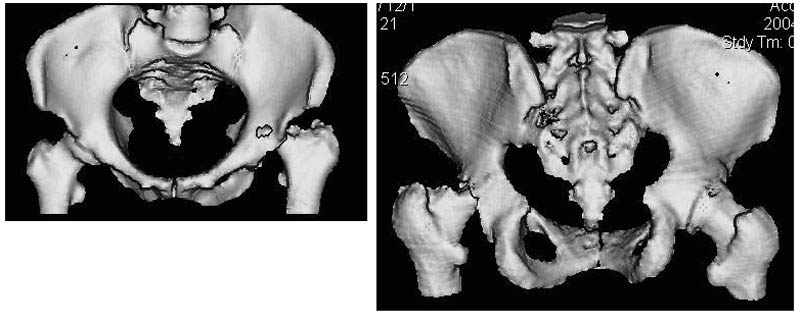

Женщина, 45 лет. В марте перенесла левосторонний коксит неизвестной этиологии. Специфику и онкологию исключили.

Интраартикулярных инъекций не было. Сейчас процесс клинически и рентгенологически - стабилизировался. Состояние вполне удовлетворительное.Предполагается тотальное эндопротезирование с пластикой полости аутокостью. Возможна ли бесцементная <чашка>? Заранее благодарю! С уважением,А.В.Владзимирский

Дополнение - проконсультировался с женой-она специалист рентгенолог - на КТ большое колиество мягкотканного компонента - ищите микоплазмы или бруцеллу. Я склоняюсь к виопсии.

Пртезирование через пол года после коксита закончившегося лизисом сустава, который на снимках выглядит как гнойный? Что значит неизвестной этиологии?